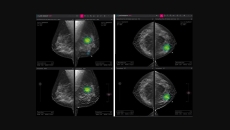

Also, South Korean startup Lunit obtains two new US FDA approvals for its AI diagnostic tools.

The company develops AI tools to analyse chest x-rays and breast mammography.

The company has developed a line of products targeting the mammography space to enable early and accurate breast cancer detection.